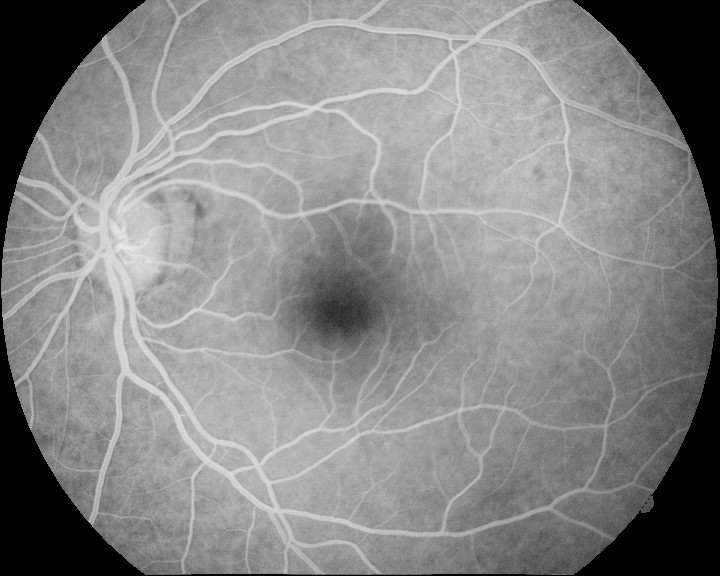

where m=1𝑚1m=1 for the angiography and m=1𝑚1m=-1 for the retinography, and subscript\lceil\cdot\rceil_{\emptyset} denotes the halfwave rectification. The rectification is used to avoid the negative Laplacian peaks outside the vessel regions so that only the vessel interiors are represented in the enhanced images. This results in a common representation for the retinography and the angiography, with enhanced vessel regions and the same intensity level pattern. Figure. 2 shows the result of the vessel enhancement operation applied to the retinography/angiography pair exposed in Fig. 1.

Refer to caption

Figure 2: Examples of the vessel enhancement operation applied to the multimodal image pair in Fig. 1: (a) result from retinography; (b) result from angiography.